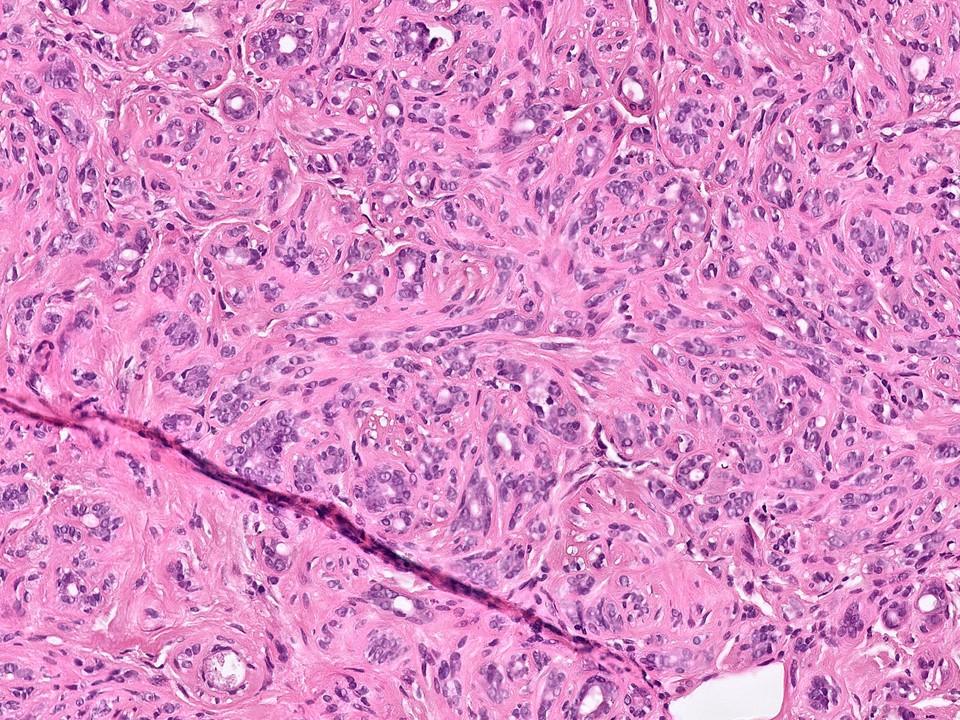

Malignant Phyllodes Tumor

Malignant phyllodes have an infiltrative border (as pictured here), highly cellular stroma, stromal cells with moderate to marked nuclear pleomorphism, and prominent mitotic activity (>/= 10 mits per 10 HPF)